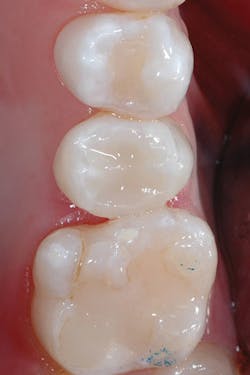

Although the bulk-fill flowable can be placed in larger increments, a small increment was placed first to ensure sufficient curing of the material at the floor of the chamber (figures 3 and 4). The next layer of SureFil SDR flow+ was placed in a 4-mm bulk increment again, followed by 20 seconds of light curing. A final layer of universal composite was placed, occlusion was checked, and after a final polish and postoperative radiograph, the patient was released (figures 5 and 6).